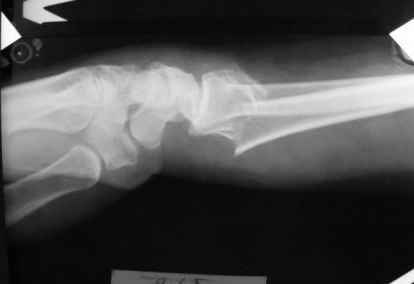

Уважаемые коллеги.Прошу обсудить случай лечения перелома дистального метаэпифиза лучевой кости. Ситуация скандальная и крайне неблагоприятная. Больная с патологической обстоятельностью мышления, склонностью к сутяжничеству, патологическими умозаключениями, не поддающимися коррекции (см. психиатрию, правда офиц. диагноза нет). В данном случае есть ряд ошибок с нашей стороны, прежде всего в отношении качества ведения документации (за что получил административное взыскание, по делом мне дураку). В остальном- придерживались в лечении подхода классический советской школы. Так как умную операцию…… сами знаете… 15.12- перелом луча в Москве. Там же репозиция, гипс. Дальнейшее лечение у нас в ЦРБ. 20.12.- вторичное смещение в гипсе21.12- под внутривенным наркозом- репозиция, гипсовая лонгета. Дальше начинается самое интересное. После репозиции больная заявила, что я (репозицию делал я) порвал ей все связки в суставе, посинел у нее 5 палец, якобы я за него тянул и т. д. На самом деле на 2 сутки после репозиции рука немного отекла и было незначительное сдавление гипсом, который был ослаблен. Дальнейшее лечение консервативное. Через 6 недель- гипс снят, назначено ЛФК. Пациентка крайне недовольна. Говорит, что на снимке у нее выступает кость, я ей сломал руку и.т.д. В общем началось. Пациентка прочитала в интернете наверное все, что есть по данной травме.По заключениями рентгенологов и консультанта из КДЦ областной больницы - стояние отломков допустимое. Объективно говоря- снижена высота лучевой кости, диастаз лучелоктевого сочленения, и не сросся шиловидный отросток. однако на РКТ при сравнении с другой стороной- разница незначительная. Дальше в одной из больниц нашей области и одной из больниц Москвы (вроде бы КГБ 53) врачи сказали, что репозиция сделана плохо. Нужна операция (восстановить длину лучевой кости), даже один из них предложил РЕДРЕССАЦИЮ (хи-хи) с наложением аппарата Илизарова. Что это для данной больной- радость неописанная. (см. описание психического статуса). Ничем другим, кроме зарабатывания дешевого авторитета объяснить данный факт не могу.Кстати, у больной еще нейропатия локтевого нерва.Для разрешения конфликта больная направлена на консультацию в ЦИТО на 03.03.11.

1. РЕПОЗИЦИЯ сделана качественно(ОСНОВНЫЕ 2 УГЛА ВЫСТАВЛЕНЫ ПРАВИЛЬНО ) , но перелом нестабильный и склонен к втор смещению . Поэтому мы стараемся все переломы со смещением фиксировать 3-МЯ спицами по GRIN методике .

1. Репозиция от 21.12.10 была выполнена лучше, чем первичная.

Заключение: Консолидированный в неправильном положении перелом дистального метафиза левой лучевой кости. Ротационная контрактура левого предплечья. Рекомендовано- разработка, консультация через 2 месяца.

3.Исходя из конкретной ситуации и здравого смысла абсолютных показаний к операции не было и сразу после травмы и нет сейчас ,уже после сращения,поскольку перелом внесуставной,а осколок по тылу луча не препятствует торцевому упору по волярному краю луча.